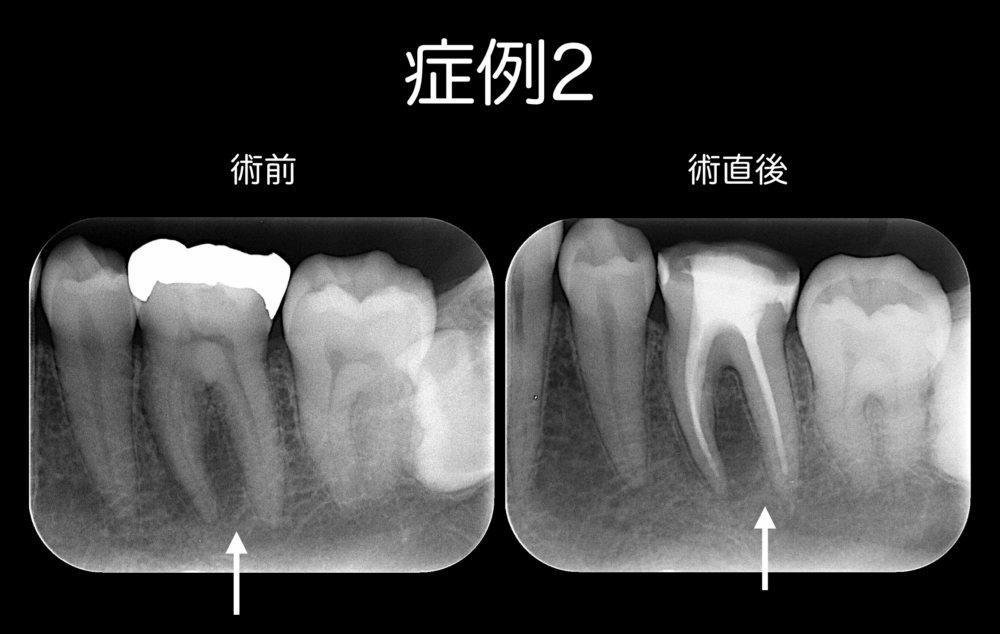

症例2の患者さんは、47歳男性です。

かむと痛みがあることを主訴に、ももこ歯科を受診されました。

原因歯は左下顎第一大臼歯(白い矢印)で根管治療を行い、直接法で築造を行いました。

この症例は、残りの歯質が十分にありましたので、ファイバーポストは入れませんでした。

症例1と同様に、根管充填も築造も歯質との隙間なくできています。